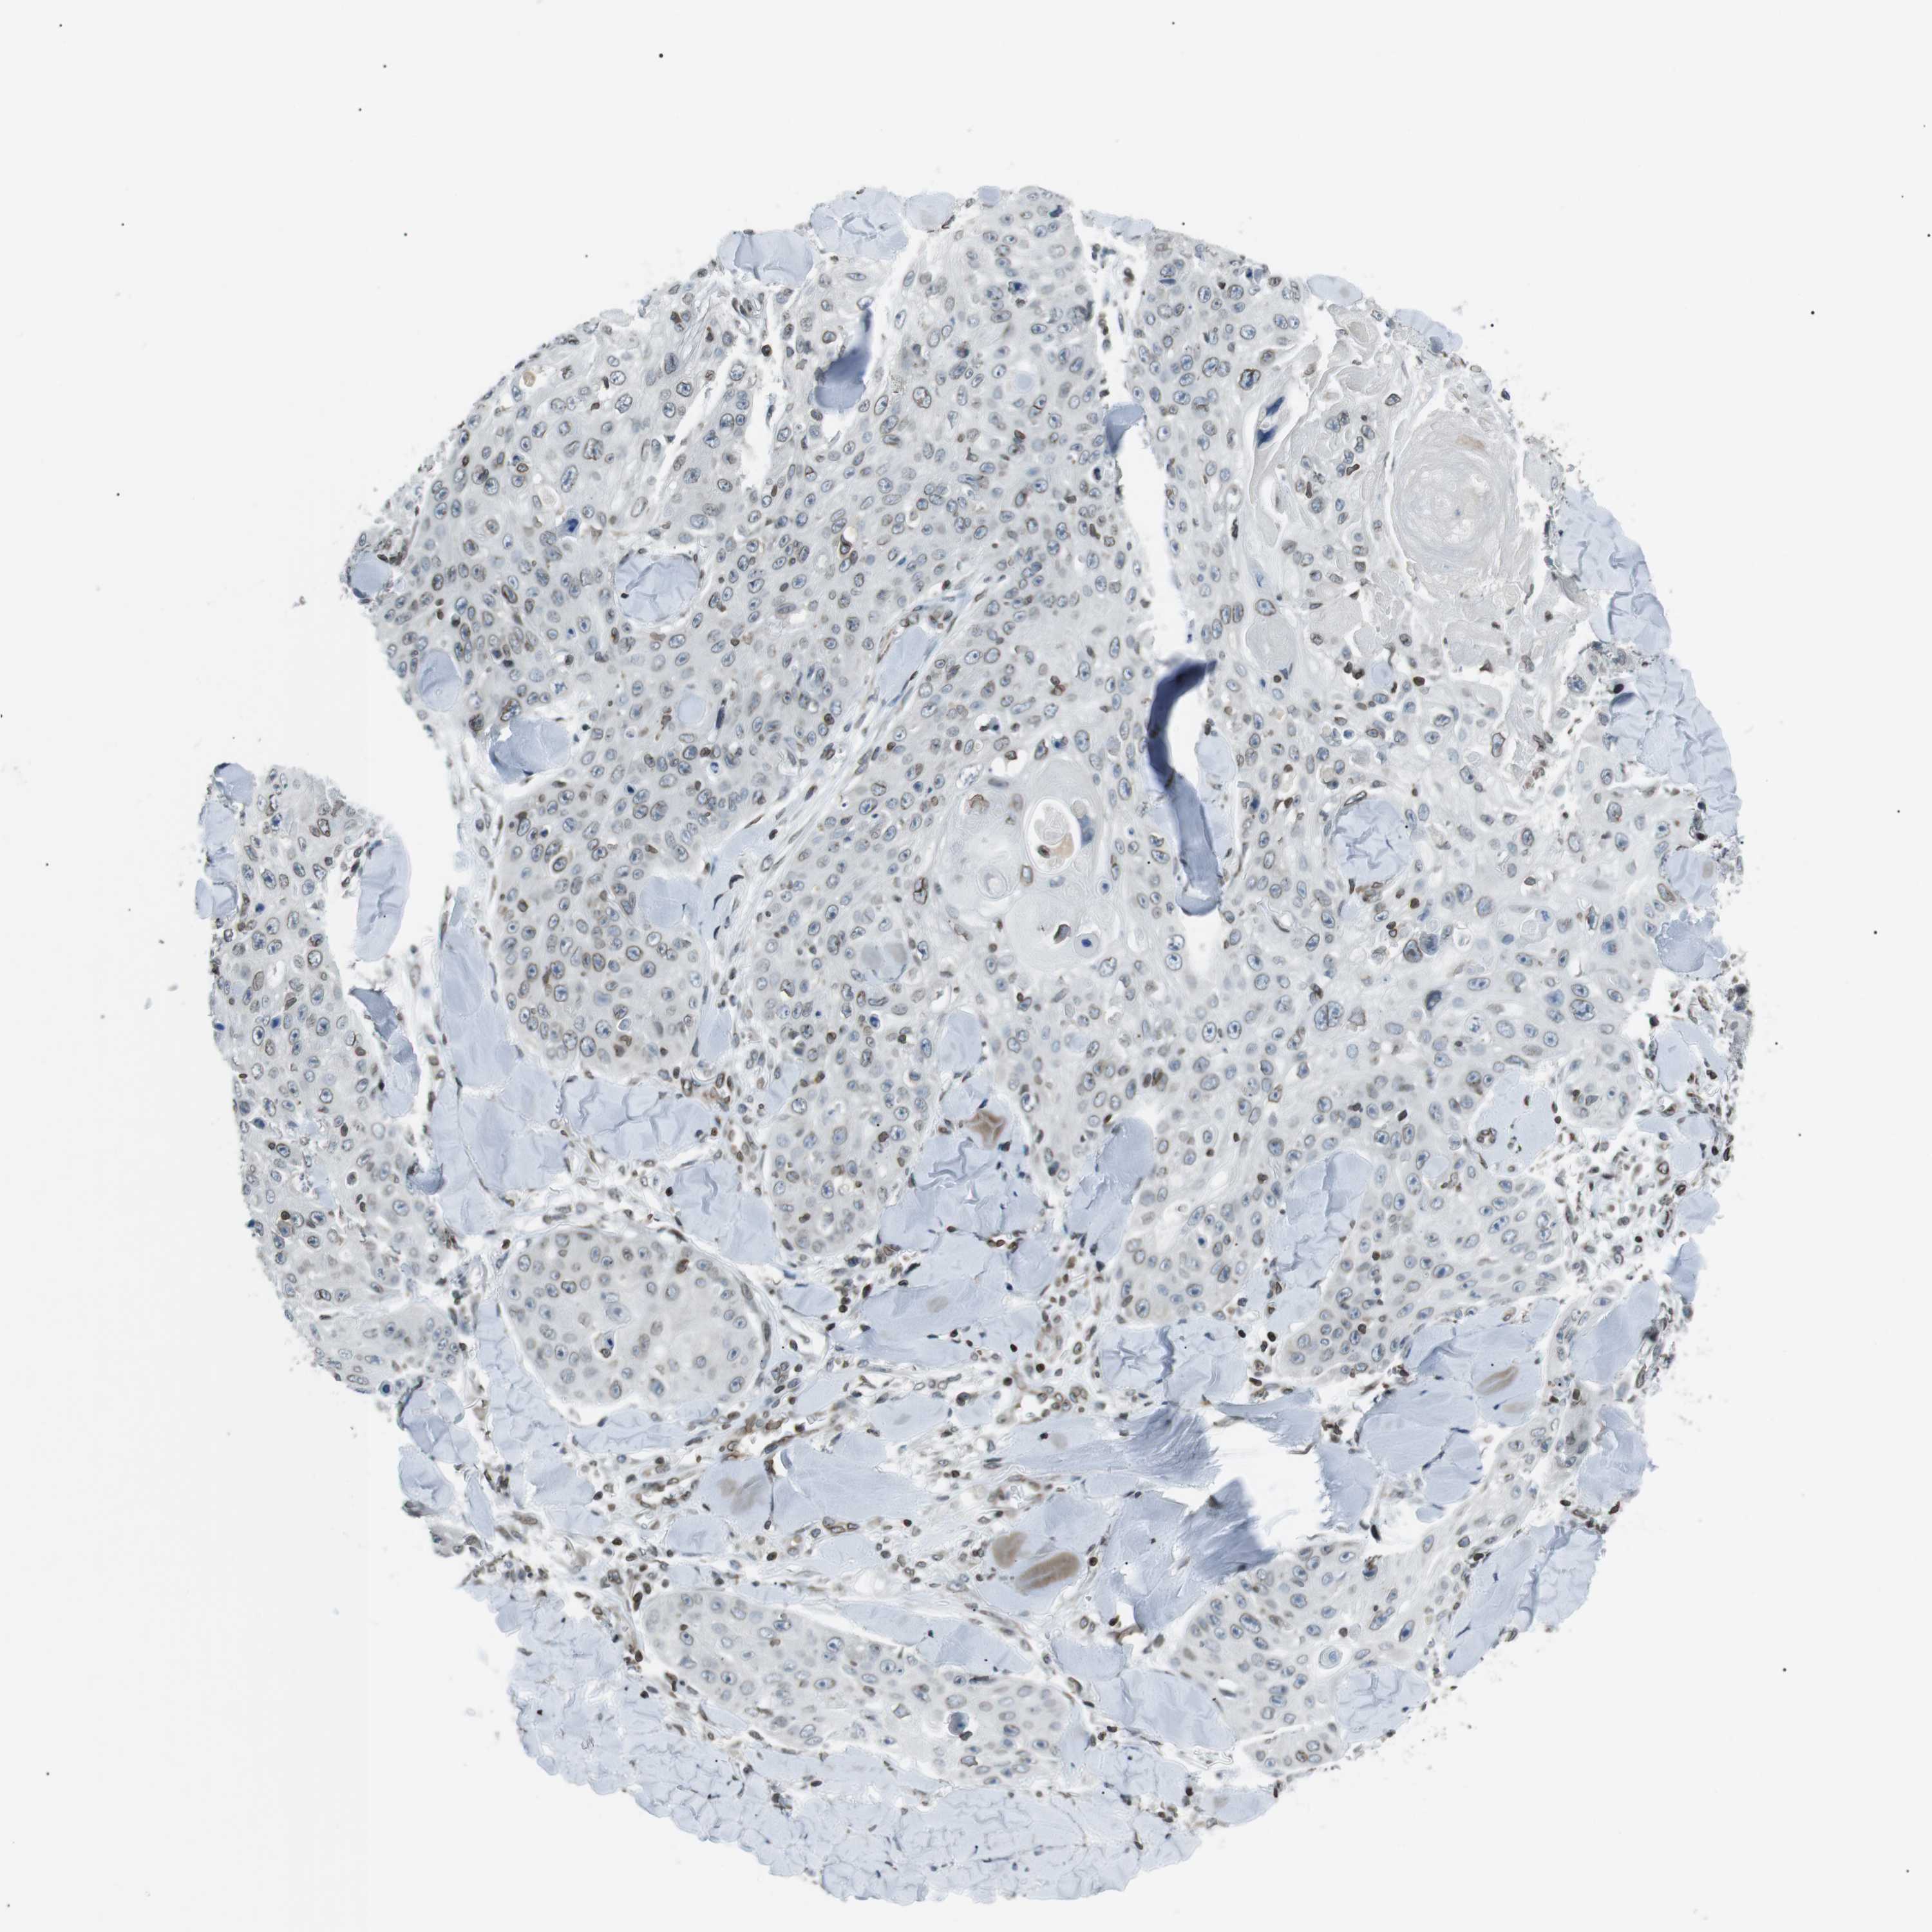

SKIN CANCER - Protein expressioni

A mouse-over function shows sample information and annotation data. Click on an image to view it in a full screen mode. Samples can be filtered based on level of antibody staining by selecting one or several of the following categories: high, medium, low and not detected. The assay and annotation is described here.

Each image is clickable and will lead to virtual microscopy that enables deeper exploration of all samples and also displays staining intensity scores, fraction scores and subcellular localization as well as patient and tissue information for each sample.

Antibody HPA015752

Staining

Medium

Intensity

Moderate

Quantity

75%-25%

Location

Cytoplasmic/membranous

Basal cell carcinoma

Squamous cell carcinoma in situ, NOS